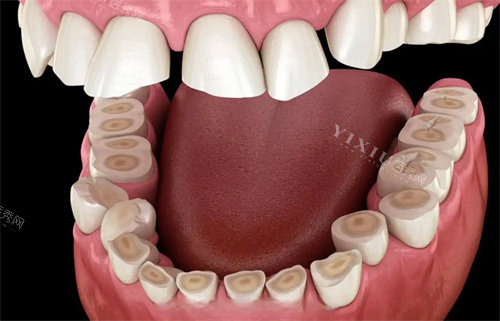

口腔种植:针对牙齿缺失患者,开展单颗、多颗以及全口种植牙项目。与多个比较有名种植体品牌合作,能满足不同患者的需求和预算。

口腔修复:不管是烤瓷牙、全瓷牙修复,还是活动义齿、固定义齿,医生都能根据患者的口腔情况,打造出美观又实用的修复结果。